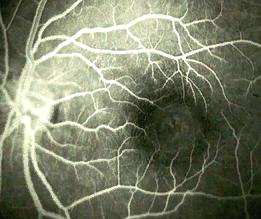

Left superior branch retinal vein occlusion. The fluorescein angiography on the left shows areas of hypofluorescence and hyperfluorescence.

Hypofluorescence - retina haemorrhages and the hard exudates block the choroidal fluorescein causing dark patches

- pre-retinal haemorrhages, in addition to blocking the choroidal fluorescein also cover the retina

vasculature

Hyperfluorescence - damaged retina veins have exposed collagen which are stained by fluorescein. Leakage around the

damaged vein occurs due to damage to the endothelium walls

- microaneurysms appear as multiple bright spots.